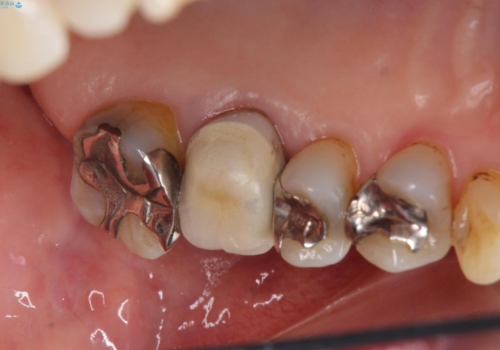

70代女性 段差のある被せ物のやり替え

その代わり、現在ある歯をしっかり治療することになり、左上下の治療を行っています。

左上56間が狭かったため、写真にはないですが、セパレーションを2回ほど行い、歯根間距離を広げてから処置を行っています。